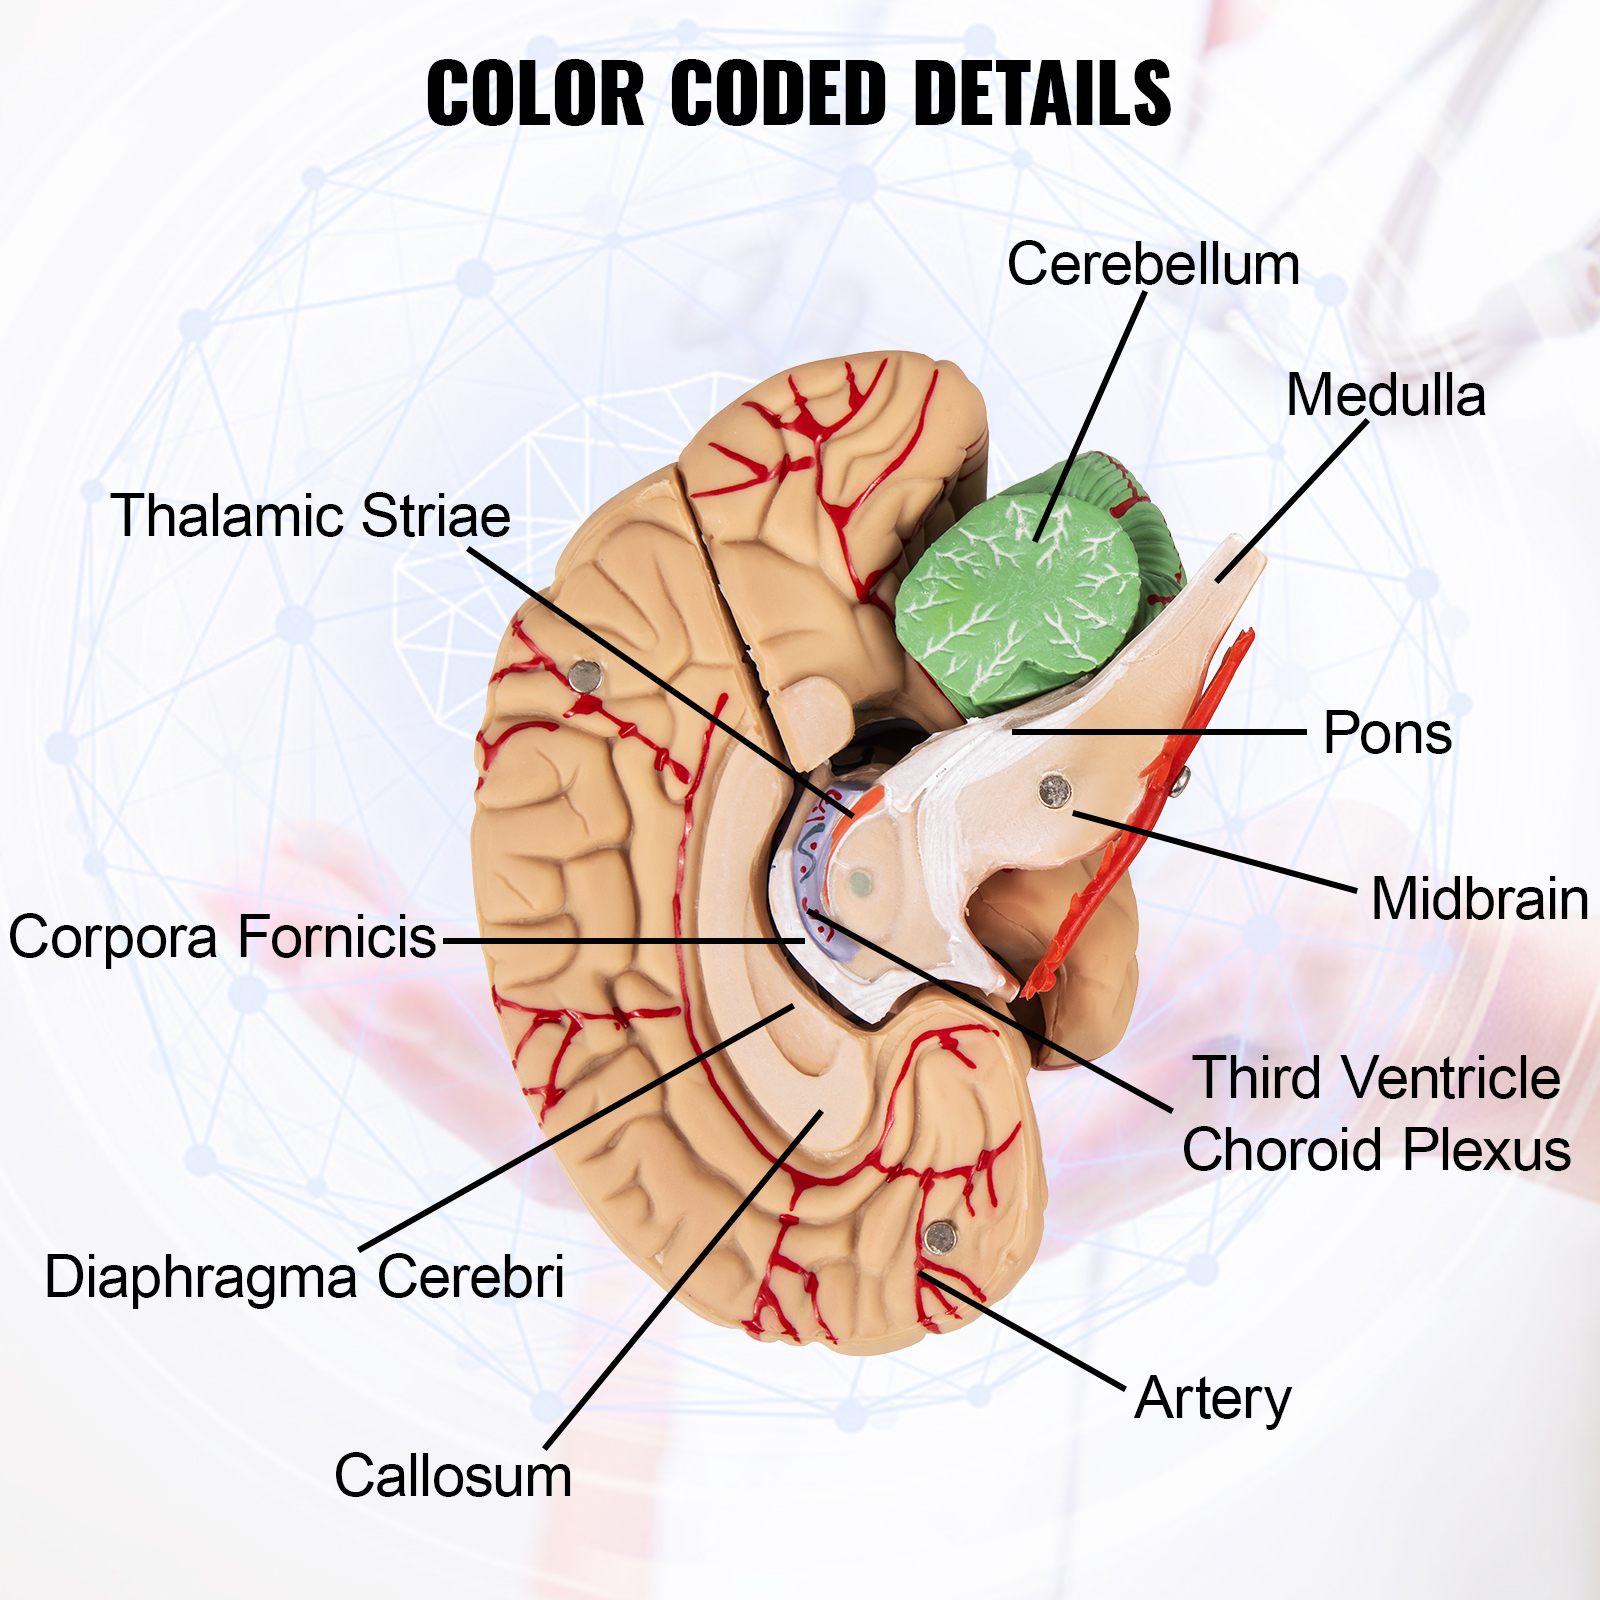

Color-Coded Details

Every functional area of the life-size brain model is hand-painted with different colors to easily identify the various parts and structures of the brain. Users can learn the basic knowledge of brain constructions through the model without effort.

Color-Coded Details

Every functional area of the life-size brain model is hand-painted with different colors to easily identify the various parts and structures of the brain. Users can learn the basic knowledge of brain constructions through the model without effort.